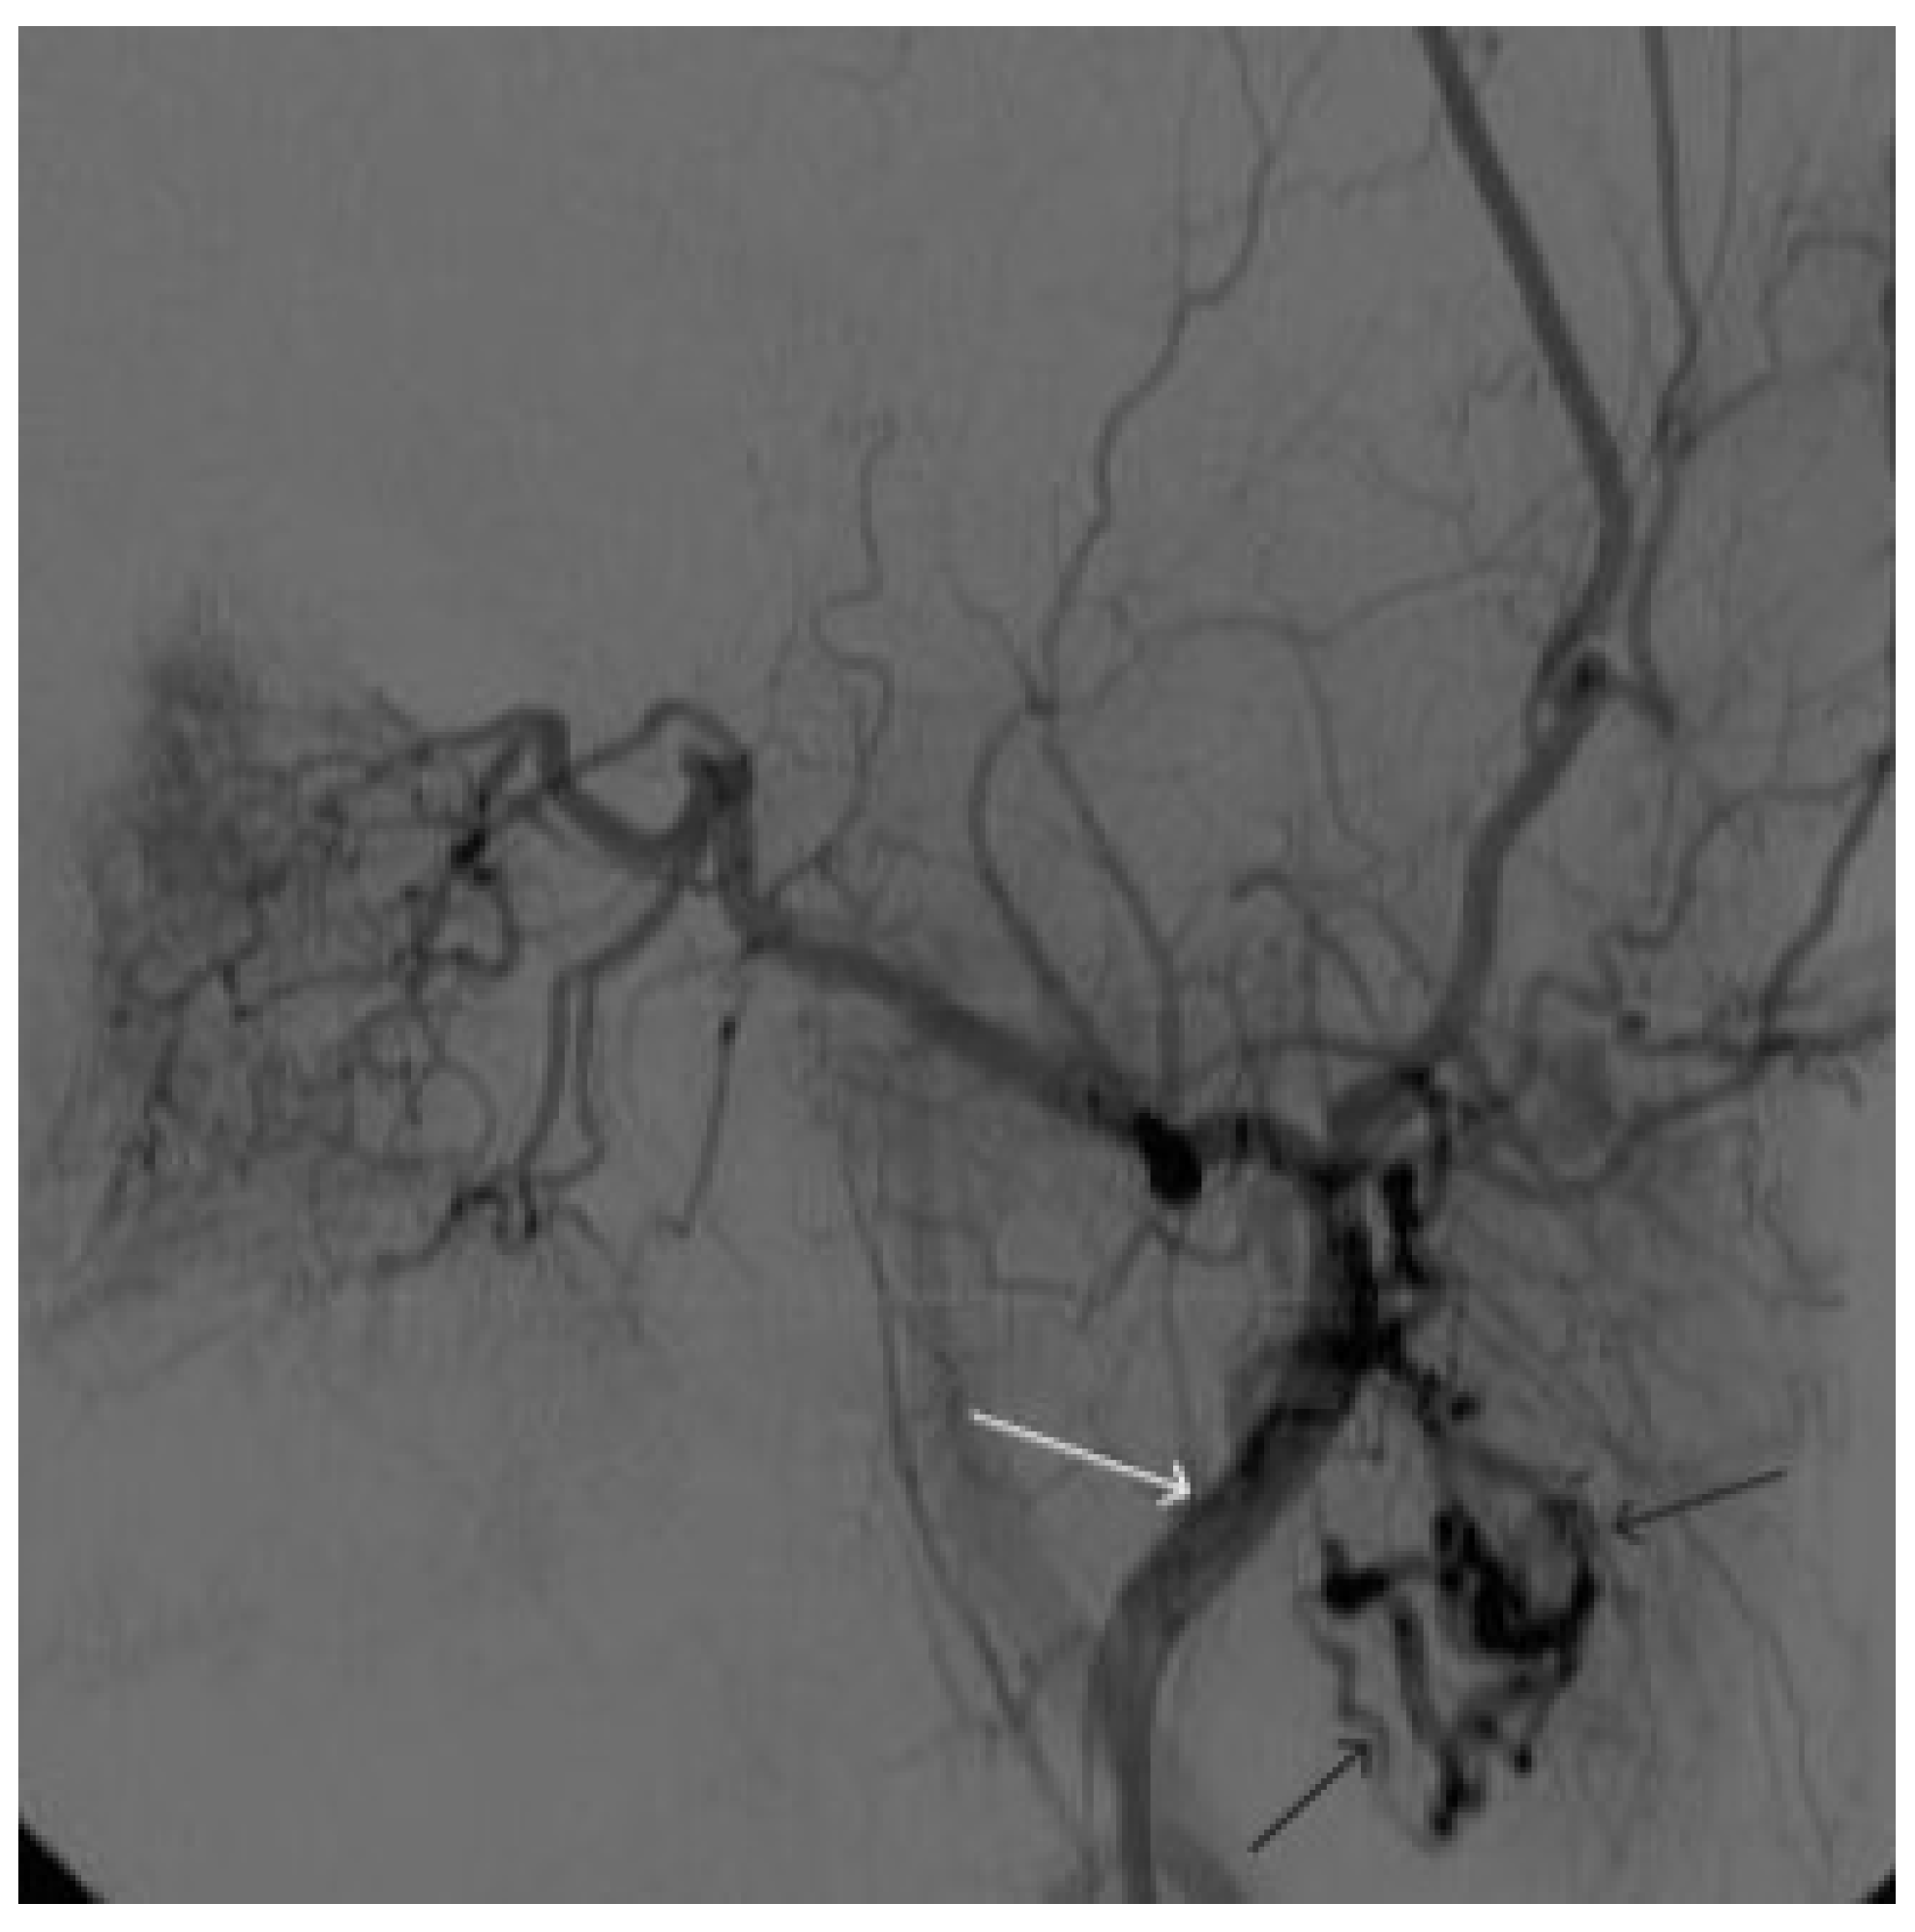

A 58-year-old male patient was admitted to the clinic complaining of a palpable formation in the left submandibular region. When angiography was performed, the filling of the vascular network of the tumor of the left submandibular region from the branches of the left occipital artery, as well as the muscular branches of the left vertebral artery, was noted (Figure 11). The patient underwent intravascular embolization of the paraganglioma with 7.5 mL of non-adhesive composition ONYX18 (Figure 12 and Figure 13). The vascular network supplying the paraganglioma was partially switched off (Figure 14). There were no complications. The mRs score at discharge was 1.

Figure 11. Digital subtraction angiography from the left common carotid artery: (a) direct projection, (b) lateral projection (white arrows indicate the left internal carotid artery, long black arrows indicate the external carotid artery, short black arrows indicate the boundaries of the paraganglioma).

Figure 14. Digital subtraction angiography from the left common carotid artery: (a) direct projection, (b) lateral projection (white arrows indicate the guiding catheter in the left external carotid artery, black arrows indicate the boundaries of the embolized paraganglioma).